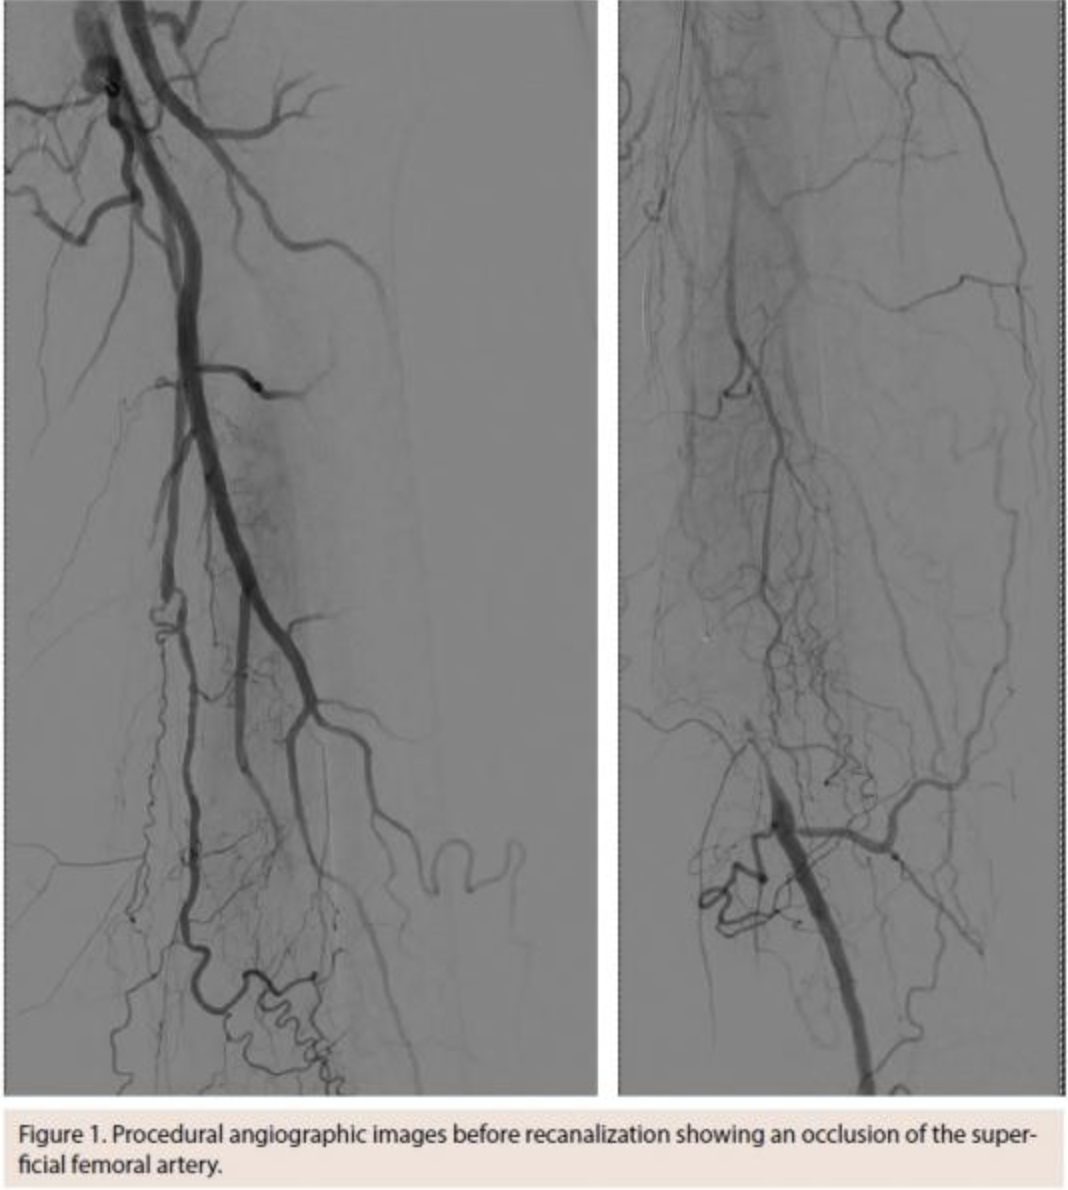

A 73-year-old male patient with a history of dyslipidemia, lower-back pain after a vertebral fracture, and nicotine abuse presented with a progressive and disabling intermittent claudication on the left side, not responding to prolonged supervised walking exercise. The patient had an ankle-brachial index of 0.68 and imaging studies showed an 18 cm-long occlusion of the superficial femoral artery (Figure 1). After recanalization, the lesion was treated with two percutaneously placed 6 mm Viabahn endoprostheses, covering the entire diseased segment (Figure 2). The postoperative course was uneventful, the ankle-brachial index normalized and the patient was discharged on the first postoperative day.